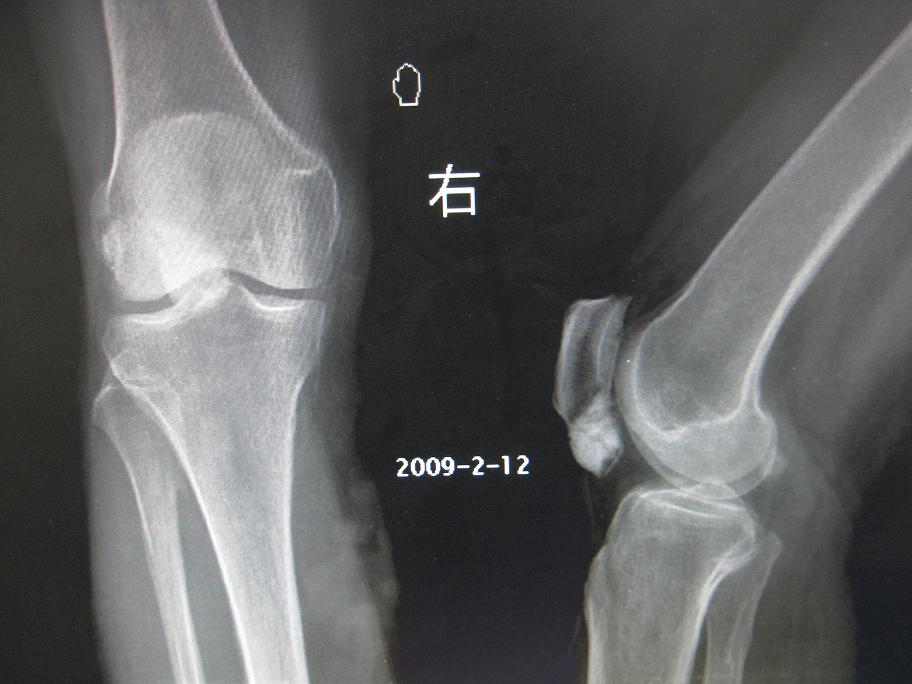

以下是引用黑白光影在2009-3-14 10:32:00的发言:[br]1、考虑髌下囊肿瘤样钙质沉着,髌骨骨软骨瘤待排, 2、膝关节退行性改变,3、小腿内侧静脉曲张?

以下是引用余辉在2009-3-14 8:17:00的发言:[br]考虑关节退变软组织钙化可能性大,不排除髌骨占位组织钙化如软骨瘤